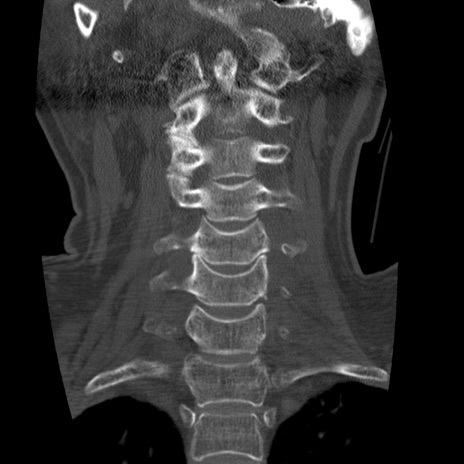

症例50 頚椎CT(冠状断像)

頚椎CT